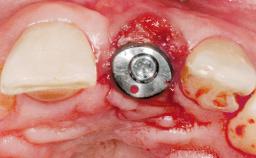

Immediate Flapless Placement of an Implant in a Maxillary Left Central Incisor Site

A 42-year-old female patient was referred to our clinic at the School of Dentistry of the University of São Paulo in November 2004, presenting a deficient restoration in the upper left central incisor. The clinical examination revealed no gingival retraction or any signs of gingival inflammation and, therefore, previous periodontal treatment was not considered. The patient presented a high lip line at full smile and a thin tissue biotype. This combination characterized a high-risk situation from an anatomic point of view, which required careful preoperative planning and cautious surgical execution.

Placement Protocol Immediate implant placement

Tooth Site Maxillary incisor or canine

Socket Morphology Single-root socket

Socket Integrity Sufficient, with intact bone walls

Bone Volume Sufficient, with intact walls